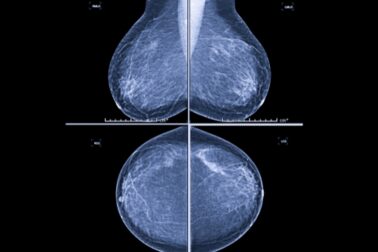

„Mikrokalcifikáty môžu byť v úplne skorom štádiu viditeľné len na mamografii, často ide o zmeny veľké len niekoľko milimetrov. Práve preto je mamografické vyšetrenie také dôležité a nenahraditeľné. Väčšie zmeny môžu byť neskôr viditeľné aj na ultrazvuku,“

vysvetľuje MUDr. Alexandra Bieliková, lekárka rádiológie AGEL Mammacentra sv. Agáty.

Lekári pri hodnotení mikrokalcifikátov sledujú viacero znakov, napríklad ich veľkosť, tvar, hustotu, rozloženie v prsníku či to, ako sa menia v čase. Práve tieto informácie pomáhajú určiť, či ide o bežný a neškodný nález, alebo o zmenu, ktorú treba podrobnejšie vyšetriť.